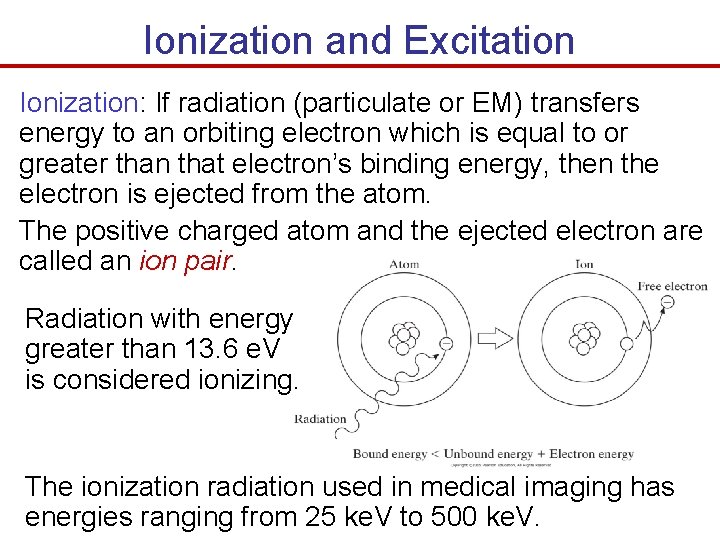

Ionization and Excitation Ionization: If radiation (particulate or EM) transfers energy to an orbiting electron which is equal to or greater than that electron’s binding energy, then the electron is ejected from the atom. The positive charged atom and the ejected electron are called an ion pair. Radiation with energy greater than 13. 6 e. V is considered ionizing. The ionization radiation used in medical imaging has energies ranging from 25 ke. V to 500 ke. V.